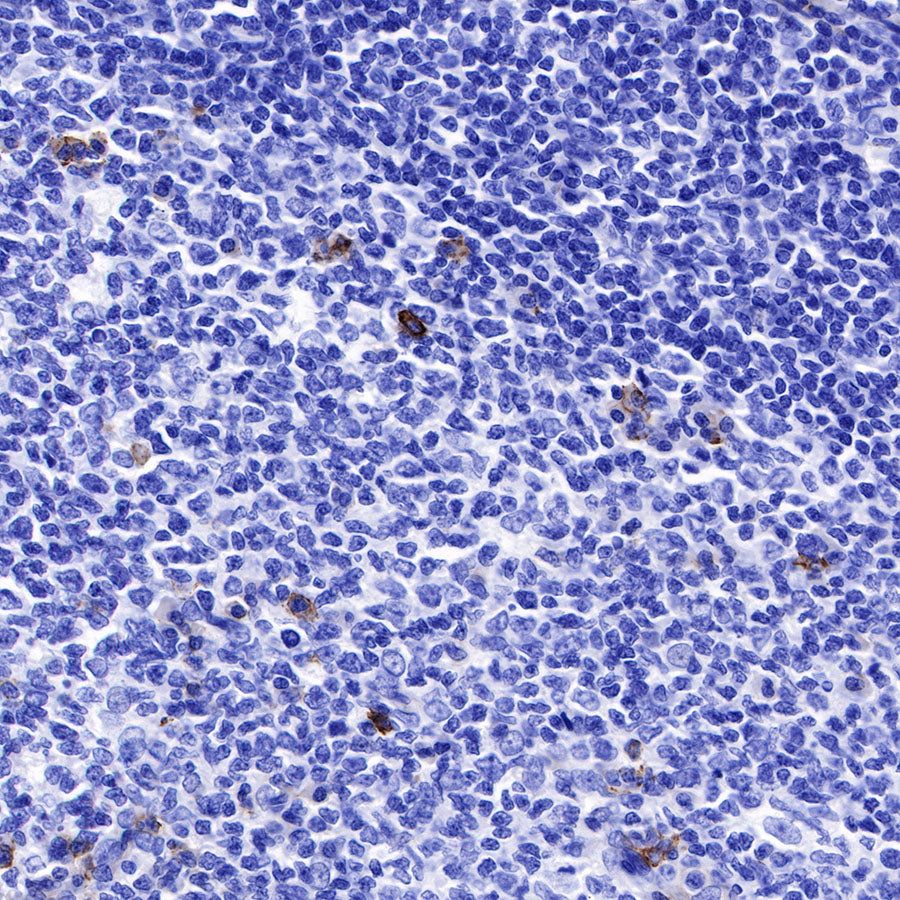

Syndecan-1 (CD138) is mostly restricted to epithelia, and bears heparan sulfate chains that are capable of interacting with a large array of polypeptides, including extracellular matrix components and potent mediators of proliferation, adhesion and migration. For this reason, it has been studied extensively with respect to carcinomas and tumor progression. Frequently, but not always, syndecan-1 levels decrease as tumor grade, stage and invasiveness and dedifferentiation increase. However, in some tumors, levels of syndecan-1 increase, but the characterization of its distribution is relevant. There can be loss of membrane staining, but acquisition of cytoplasmic and/or nuclear staining that is abnormal. Moreover, the appearance of syndecan-1 in the tumor stroma, either associated with its cellular component or the collagenous matrix, is nearly always a sign of poor prognosis [PMID: 33921767].

Picture

Immunohistochemistry